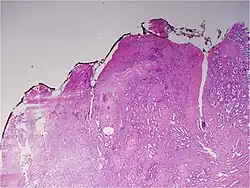

Histologic patterns

A pathologist microscopically examines the biopsy specimen for certain "Gleason" patterns. These Gleason patterns are associated with the following features:

- Pattern 1 – The cancerous prostate closely resembles normal prostate tissue. The glands are small, well-formed, and closely packed. This corresponds to a well differentiated carcinoma.

- Pattern 2 – The tissue still has well-formed glands, but they are larger and have more tissue between them, implying that the stroma has increased. This also corresponds to a moderately differentiated carcinoma.

- Pattern 3 – The tissue still has recognizable glands, but the cells are darker. At high magnification, some of these cells have left the glands and are beginning to invade the surrounding tissue or having an infiltrative pattern. This corresponds to a moderately differentiated carcinoma.

- Pattern 4 – The tissue has few recognizable glands. Many cells are invading the surrounding tissue in neoplastic clumps. This corresponds to a poorly differentiated carcinoma.

- Pattern 5 – The tissue does not have any or only a few recognizable glands. There are often just sheets of cells throughout the surrounding tissue. This corresponds to an anaplastic carcinoma.

In the present form of the Gleason system, prostate cancer of Gleason patterns 1 and 2 are rarely seen. Gleason pattern 3 is by far the most common.

The Gleason grade of architectural pattern is sometimes referred to as the Gleason architectural pattern.

The Gleason grade is based on tissue architectural patterns rather than purely cytological changes. These tissue patterns are classified into 5 grades, numbered 1 though 5. Lower numbers indicate more differentiation, with pattern 5 being the least differentiated.[4][7] Differentiation is the degree to which the tissue, in this case the tumor, resembles native tissue. Greater resemblance (lower grade) is typically associated with a better prognosis.